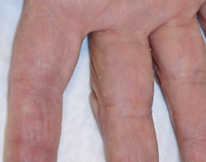

Punctate Keratoderma

Hazem Mohamed Yassin, MD; Rabab Mohamed Radwan, MD

<div id="article-content-body"> <p>Since his twenties, a 71-year-old man had had multiple tiny, pinhead, whitish yellow papules on his palms. They were asymptomatic but made his skin...